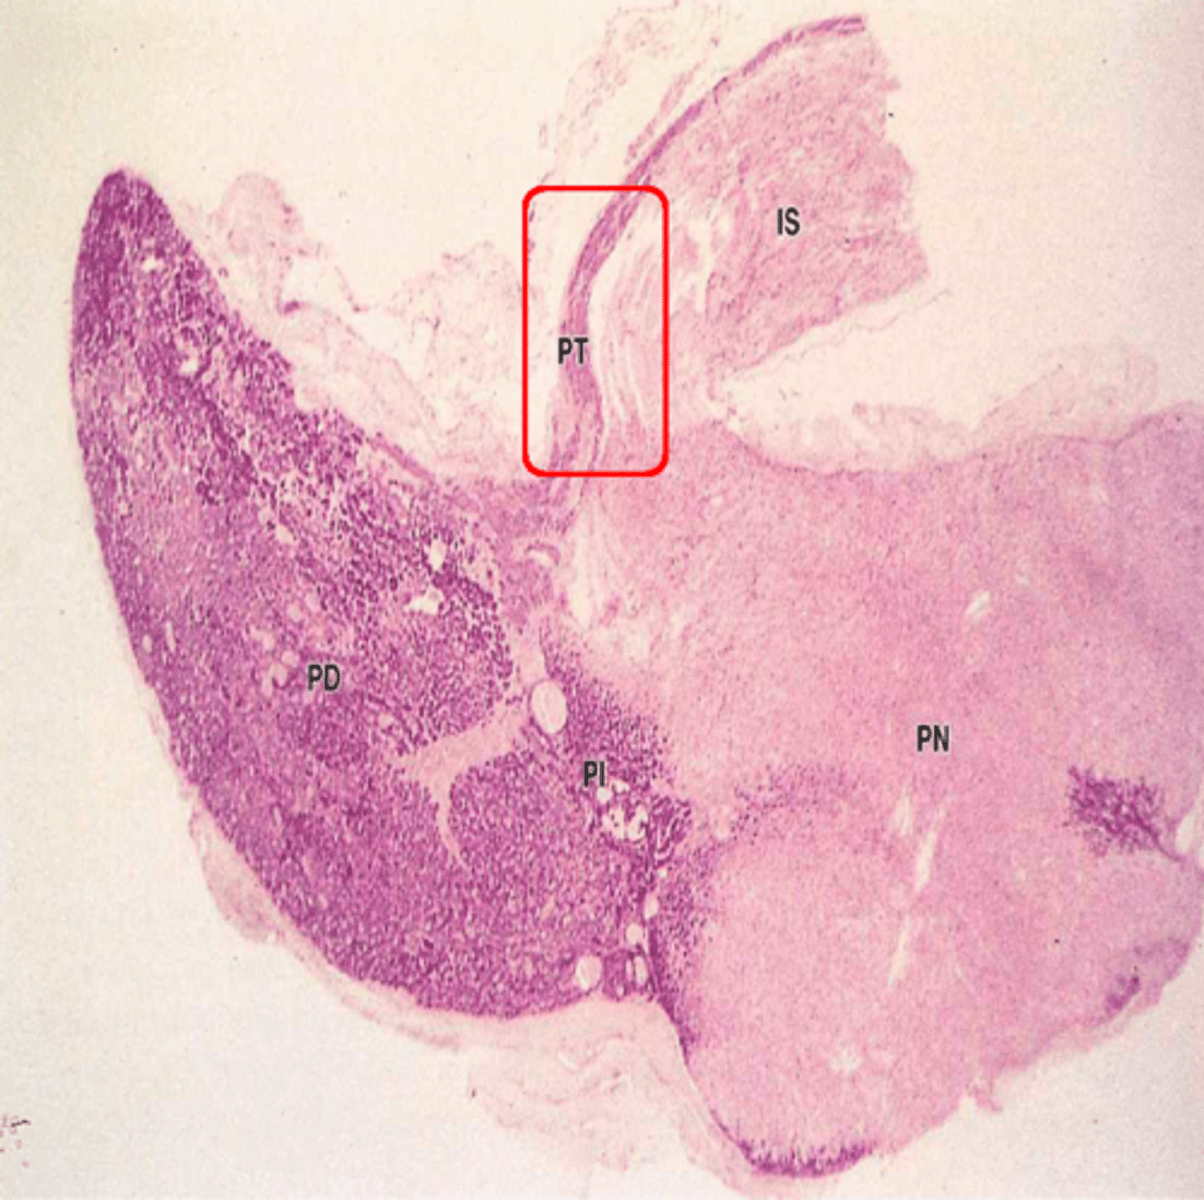

pars intermedia

What part of the pituitary:

-posterior portion of the anterior pituitary

-in contact with neural tissue

-most active during fetal development

basophils, chromophobes, and colloid filled cysts (remnants of embryonic hypophyseal pouch)

components of pars intermedia

pars tuberalis

-part of anterior pituitary that wraps around the infundibulum

-composed of epithelial tissue within a thin wrapping of connective tissue

anterior pituitary

ID dark-stained tissue

posterior pituitary

ID light-stained tissue